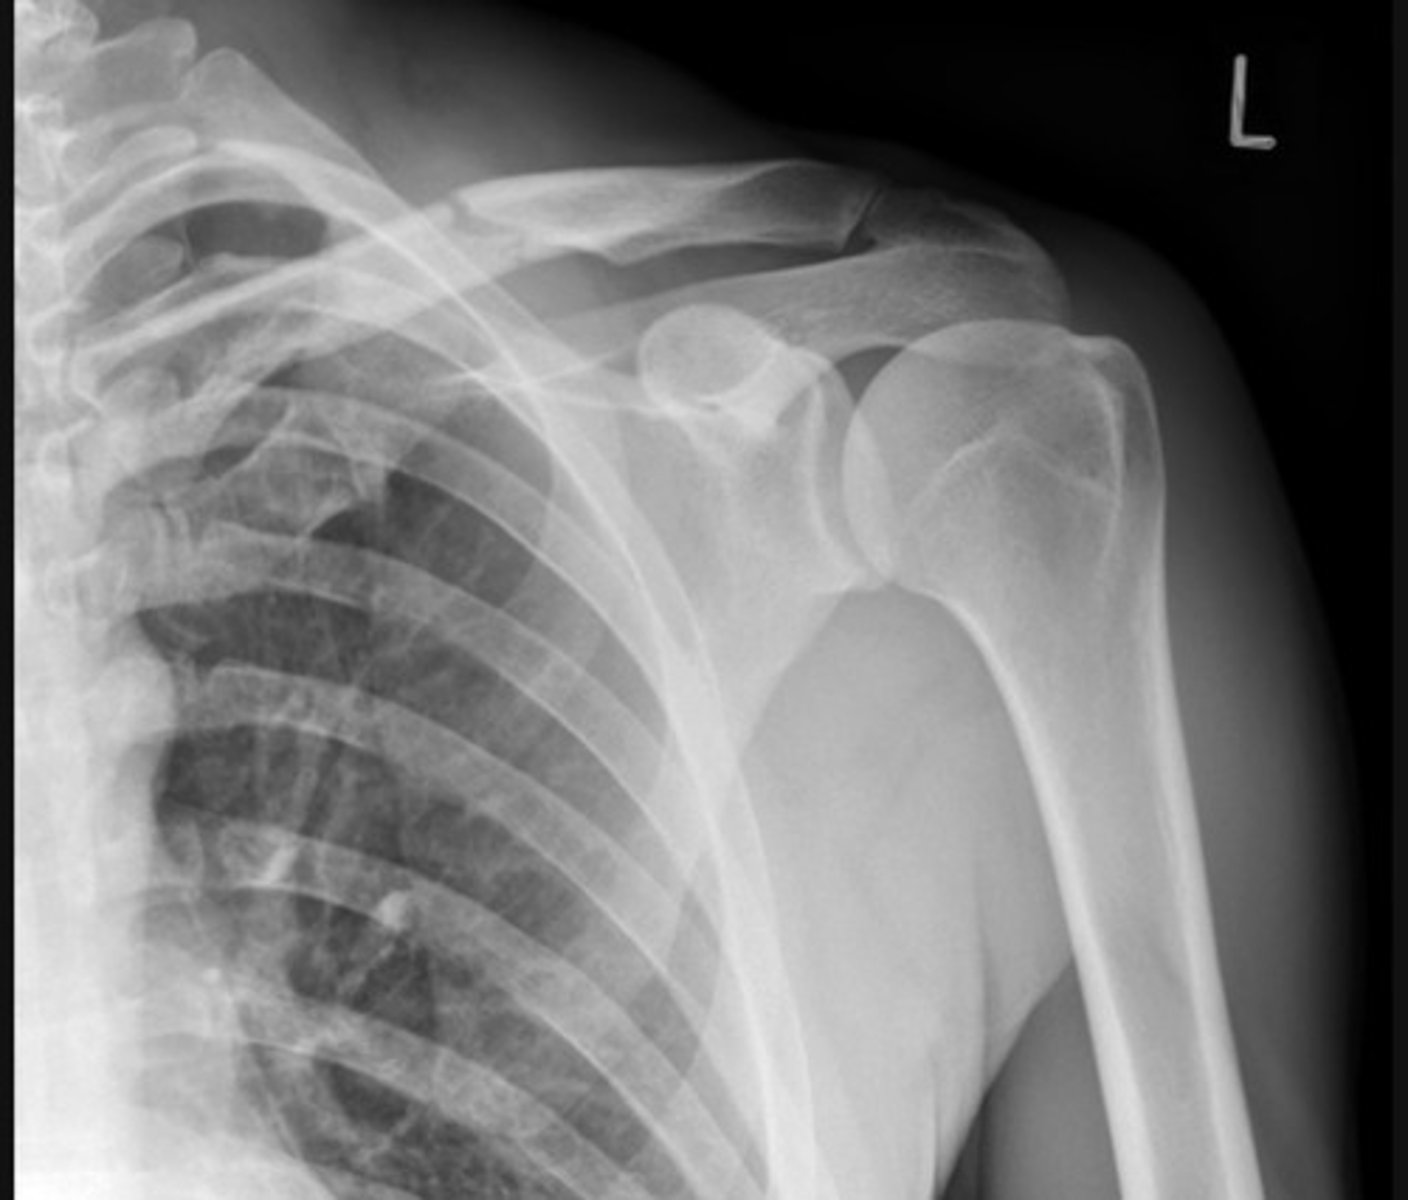

Anterior dislocation. The humeral head is dislocated from the glenoid of the scapula and is now located inferior to the coracoid process of the scapula.